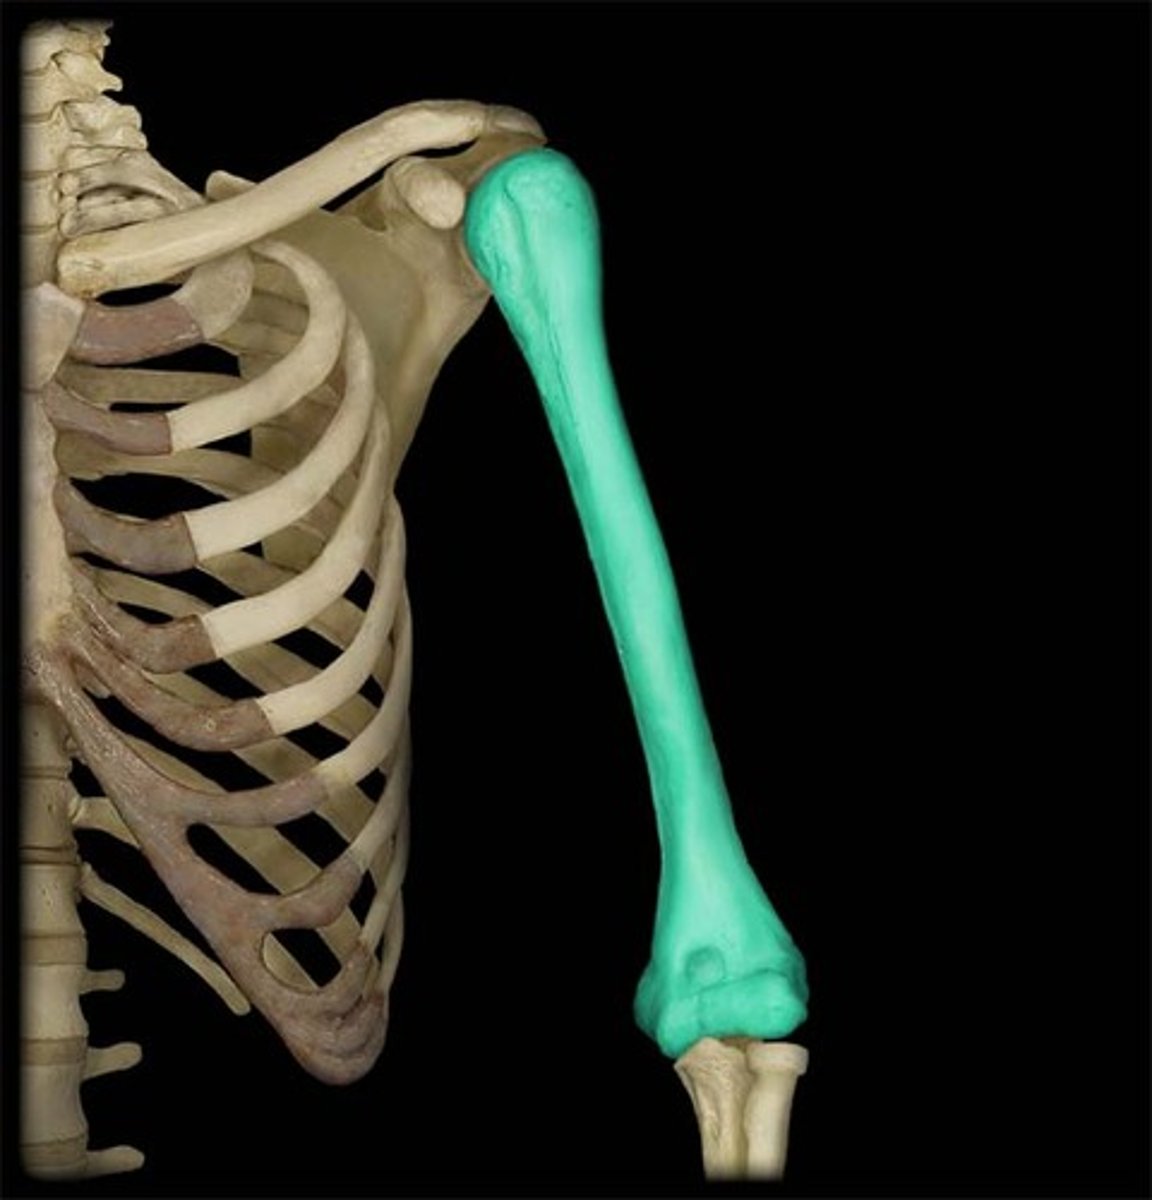

The humerus is the ______ bone in the UE

largest

What bones do the humerus articulate with?

- scapula via glenohumeral joint

- radius & ulna via elbow joint

Features of the humerus: